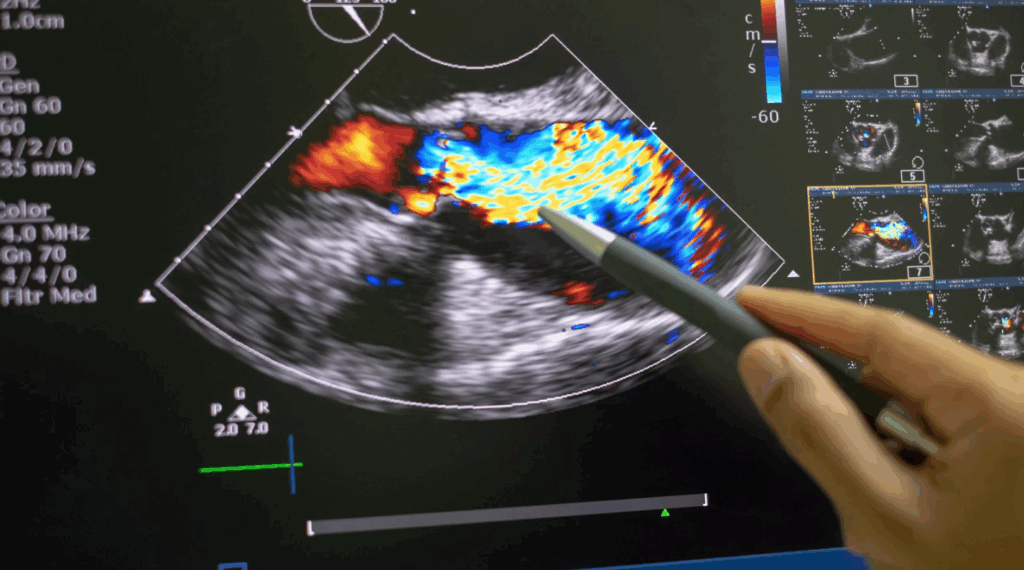

Agendar ecocardiograma com Doppler colorido em São Paulo na Clínica Bellit

Se você sente palpitações, dor no peito, falta de ar ou precisa monitorar a saúde do seu coração, é fundamental agendar um ecocardiograma com Doppler colorido em São Paulo. Esse exame é um dos mais completos para avaliar o funcionamento do coração em tempo real, identificando doenças que muitas vezes não apresentam sintomas iniciais. Na […]